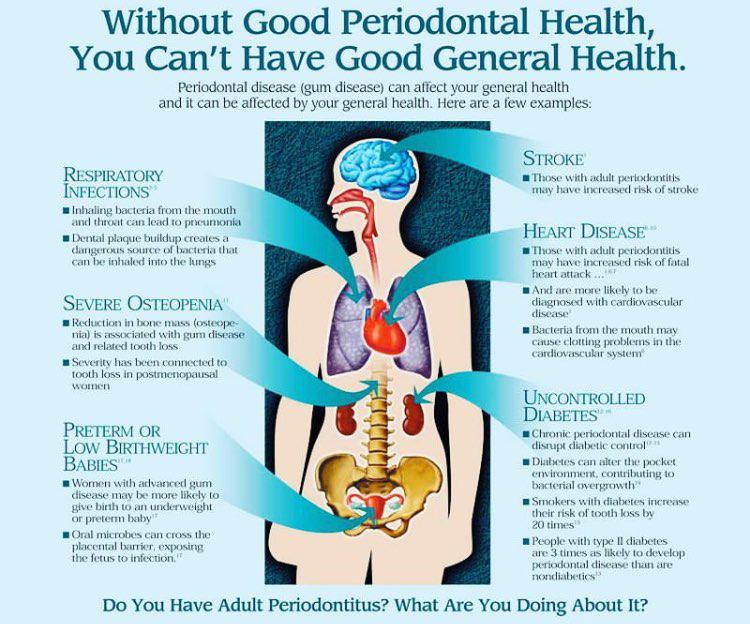

پریودنتیکس (Periodontics ) شاخهای از دندانپزشکی است که بر پیشگیری، تشخیص و درمان بیماریها و شرایطی که بر ساختارهای نگهدارنده دندانها، بهویژه لثه و بافتهای اطراف آن تأثیر میگذارند، تمرکز دارد. واژه پریودنتیک از دو واژه یونانی «peri» به معنای اطراف و «odont» به معنای دندان گرفته شده است. بنابراین پریودنتیکس یعنی مراقبت از بافت های اطراف دندان که مسئول نگهداری از آن هستند.

پریودنتیست (periodontist ) دندانپزشکی است موفق به دریافت مدت پریودنتولوژی شده و در پیشگیری، تشخیص و درمان بیماری های پریودنتال تخصص دارد. این متخصصان در درمان بیماری هایی مانند بیماری لثه، تحلیل رفتن لثه و آبسه های پریودنتال متخصص هستند. پریودنتیست ها از نزدیک با دندانپزشکان عمومی و سایر متخصصان دندانپزشکی برای ارائه مراقبت های بهداشتی جامع دهان و دندان همکاری می کنند.